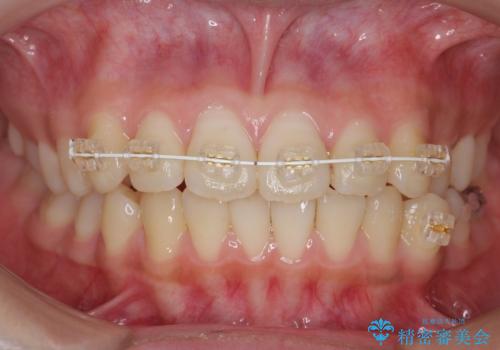

先にワイヤーで部分矯正を行ってから、インビザラインの部分矯正を行いました。

先に難しい部分をワイヤー矯正することで、インビザラインの部分矯正コースで短期間で予算も抑えて確実に治すことができます。

専門的な話になりますが、下顎の小臼歯は円柱状の形をしており、インビザライン単独では捻転はほぼ治りません。

今回は左下の小臼歯が捻転が強く、そこが反対咬合になっていたため事前に部分矯正を行いました。